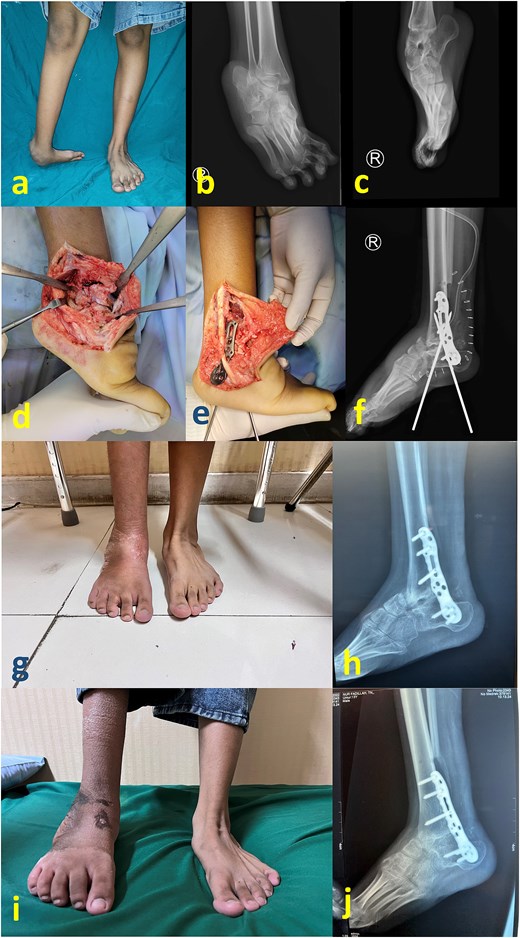

A 19-year-old woman presented with a crooked ankle and foot resulting from an untreated childhood clubfoot (Fig. 2a–c). The cause of this neglect was delayed diagnosis and treatment, as there was limited access to adequate healthcare facilities in her remote hometown.

(a) Preoperative clinical images; (b) and (c) preoperative radiograph; (d) intraoperative image after partial talectomy followed by (e) fixation with plate and screw; (f) immediate postoperative image depicting additional fixation with Schanz screw; (g) clinical images at 2 months postoperative (h) 2 months postoperative radiograph; (i) latest clinical images after 1 year postoperative; (j) latest radiograph after 1 year postoperative showing healed arthrodesis.

Similar to the first case, surgery via the transfibular approach, posteromedial tissue release, reduction facilitated by partial talectomy and tibiotalocalcaneal plate fixation were performed (Fig. 2d and e). For this patient, the fixation was reinforced with two Schanz screws that were inserted from the calcaneal plantar side (Fig. 2f). Compared with the first case, this patient’s leg was thinner with less deforming forces such that an external fixator was deemed unnecessary. Another reason for not removing these Schanz screws was to prevent the patient from prematurely bearing weight on the affected foot, as postoperative follow-up monitoring would be technically hindered. At 2 months postoperation, the Schanz screws were removed. The patient was allowed to gradually bear weight, transitioning from partial to full weight-bearing (Fig. 2g and h). Full healed arthrodesis with stable plantigrade ankle was achieved at 1 year postoperative follow-up (Fig. 2i and j).